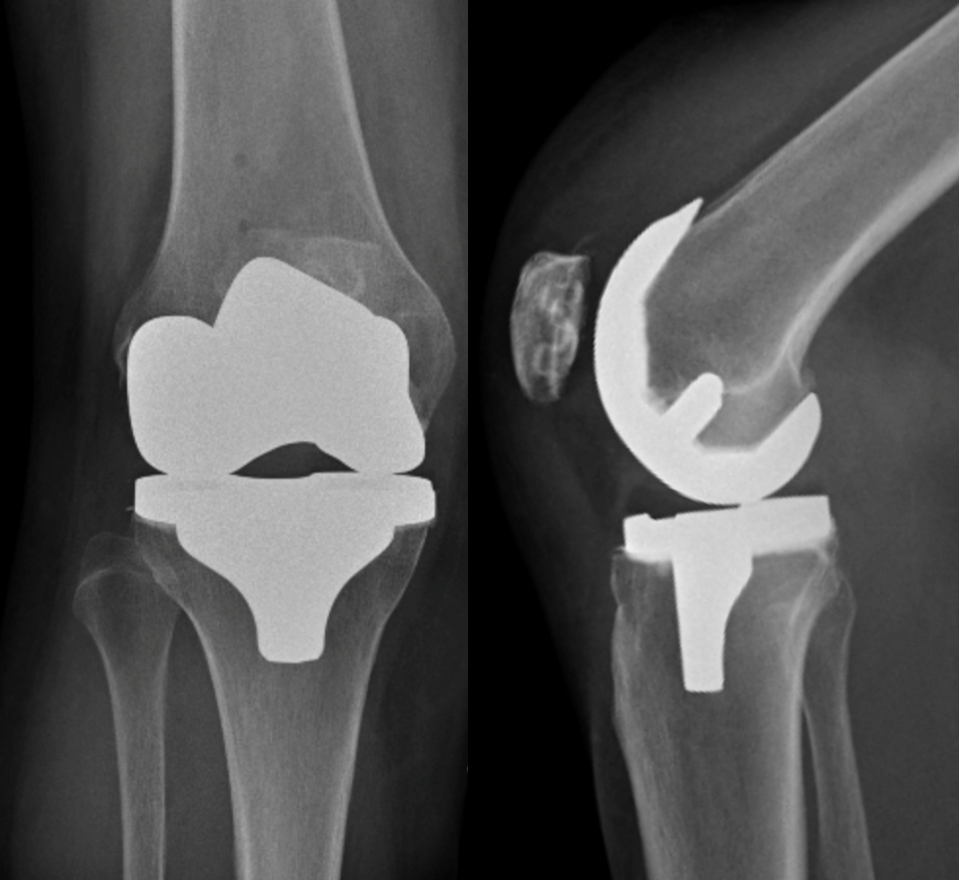

The surgery is performed through a vertical incision at the front of the knee and the patella (knee-cap) moved to the side. Approximately 9mm of bone at the end of the femur (thigh bone), and 9mm at the top of the tibia (shin bone) are removed using precise instruments.

This bone is replaced with a metal cap on the end of the femur, and a metal tray on the top of the tibia. The metal components are held securely in place with bone cement. Two or three of the main ligaments around the knee are preserved.

A plastic liner is inserted between the components to allow the bones to move smoothly on each other. The undersurface of the patella (knee-cap) is usually replaced with a plastic button. The wound is closed with absorbable sutures below the skin.

The components are inserted to optimize alignment, fit, and the stability and balance of the patient’s own ligaments and soft-tissue around the knee. Robotic-assisted knee replacement allows for very accurate planning and execution of excellent alignment, fit and tissue balance.